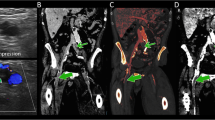

There were 28 cases of neoplastic and 16 cases of bland PV thrombi in the entire study cohort, of which 9 neoplastic and 12 bland thrombi cases were histopathologically proven, respectively. The maximum thrombus diameter and the iodine indices (I T, I T/I A, and I T/I P) of the neoplastic (n = 28) and bland (n = 16) groups in the entire study cohort are summarised in Table 2. The thrombus diameter and iodine indices observed from the neoplastic group were significantly higher than those of the bland group (Figs. 2, 3, and 4). In the subgroup of patients with histopathologically proven thrombi, the number of TP, TN, FP and FN cases, sensitivities, specificities, and AUCs at optimal thresholds of CT features scale and iodine indices are summarised in Table 3. When at least one CT feature in Table 1 was applied as the threshold, the sensitivity and specificity of the CECT characterisation of neoplastic from bland PVT were 88.9 % and 83.3 %, respectively. When at least two CT features were applied, the sensitivity and specificity were 66.7 % and 100 %, respectively. DESCT with material decomposition correctly characterised all but one case of bland thrombus with cavernous transformation of PV using I T > 1.14 mg/mL as the optimal threshold. The overall differential diagnostic performances of iodine indices were slightly, but not significantly, greater than that of the CT features scale derived from conventional CECT imaging in the histopathologically proven population.

Histopathologically proven neoplastic thrombi in a 64-year-old man with liver cirrhosis and superimposed HCC in segments V and VI (not shown). Transverse (a) arterial phase and (b) portal venous phase monochromatic CT images at 70 keV depicting the right anterior and posterior branches of PV thrombi (arrows) without clear evidence of HCC infiltration, arterial hypervascularity, or an expansile PV branch. (c) A relatively high intrathrombus iodine density is observed in the iodine-based material decomposition image